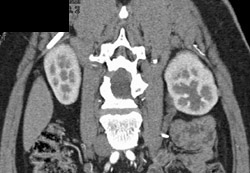

Ureteropelvic Junction (UPJ) Obstruction